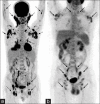

Generalized lymphadenopathy is a common and often vexing clinical problem caused by various inflammatory, infective and malignant diseases. We aimed to review briefly and highlight the potential role of (18)F-2-fluoro-2-deoxy-glucose ((18)F-FDG) positron emission tomography/computed tomography (PET/CT) in such patients. (18)F-FDG PET/CT can play an important role in the management of generalized lymphadenopathy. It can help in making an etiological diagnosis; can detect extranodal sites of involvement and employed for monitoring response to therapy.